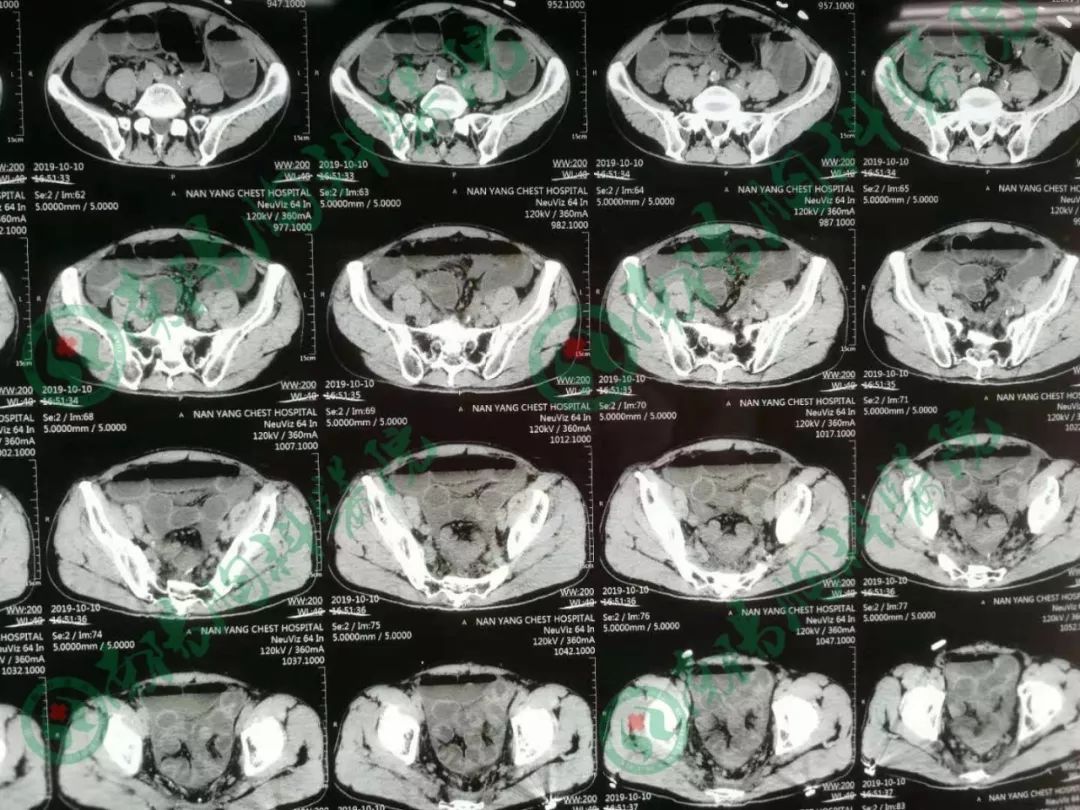

患者经过立位DR和CT检查均提示肠管高度扩张,多发阶梯状液平,病情非常棘手。

告知急诊手术,术中探查见小肠高度扩张,末段回肠扭转粘连于盆底骶前,放射性肠炎改变,呈冻结状,部分肠管受压坏死,行末段冻结扭转回肠切除术,小肠造瘘术,术后病人生命体征平稳,安返ICU。